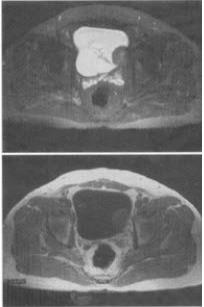

- 单项选择题1、 男,59岁,血尿1个月,MRI检查如图所示。最可能的诊断是()。

A、膀胱内血块

B、膀胱癌

C、膀胱结石

D、膀胱息肉

E、输尿管囊肿